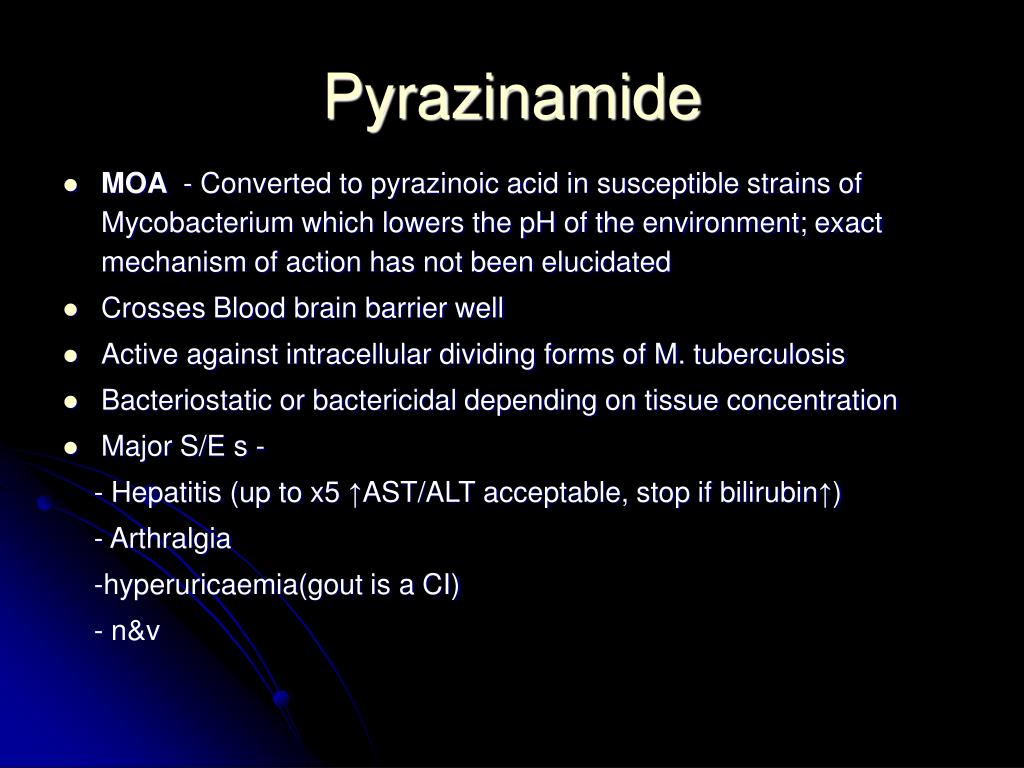

A six months regimen containing isoniazid (H), rifampicin (R) and pyrazinamid (Z) daily for two months, followed by H and R daily for another four months (2HRZ/2HR) has been proven effective for the treatment of pulmonary tuberculosis, provided the cause is a fully susceptible strain of M. tuberculosis.

The most common TB medicines are: isoniazid pyrazinamide ethambutol (Myambutol) rifampin (Rifadin)

Apr 03, 2021 · The most common medications used to treat tuberculosis include: Isoniazid Rifampin (Rifadin, Rimactane) Ethambutol (Myambutol) Pyrazinamide If you have drug-resistant TB, a combination of antibiotics called fluoroquinolones and injectable medications, such as amikacin or capreomycin (Capastat), are generally used for 20 to 30 months.

If you have an active TB disease you will probably be treated with a combination of antibacterial medications for a period of six to 12 months. The most common treatment for active TB is isoniazid INH in combination with three other drugs—rifampin, pyrazinamide and ethambutol.Apr 8, 2020

Most common TB drugs Isoniazid. Rifampin (Rifadin, Rimactane) Ethambutol (Myambutol) Pyrazinamide.Apr 3, 2021